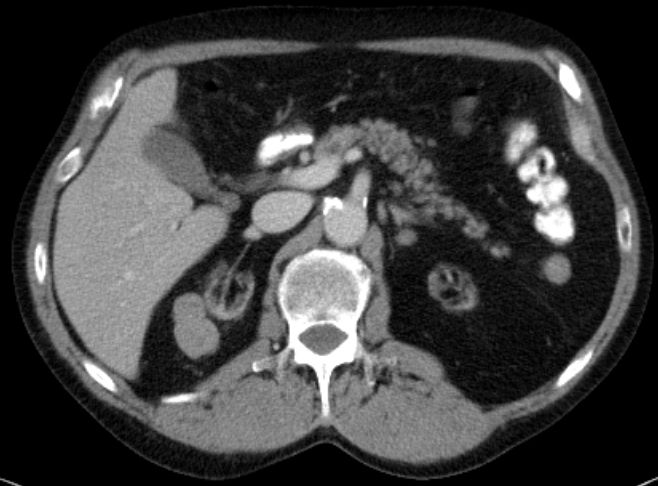

| Metastasierung | 65-jähriger Mann mit primär metastasiertem Merkelzelltumor.

Metastase lateral der rechten Restniere und

unterhalb des Colon descendens. ![]() |